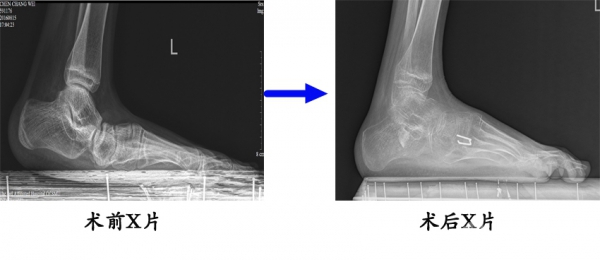

6.脑瘫平足的治疗。16岁男性患者,脑瘫伴左侧平足,术前左足侧位X线片,见跟骨向下倾斜,“中足断裂”,足弓消失。矫正术(跟骨延长、跖内侧紧缩、内侧楔骨截骨)后,可见跟骨倾角恢复正常,足弓重建。